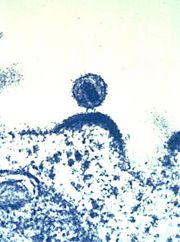

Sich aus einer Immunzelle herauslösendes HI-Virus.